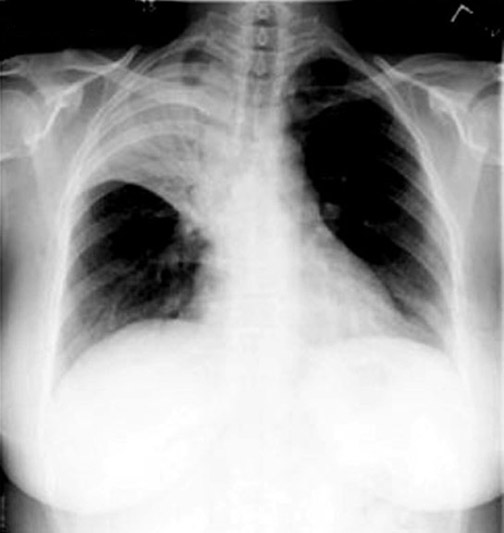

|  | Air Bronchogram In a normal chest x-ray, the tracheobronchial tree is not visible beyond the 4th order. As the bronchial tree branches, the cartilaginous rings become thinner, and eventually disappear in respiratory bronchioles. The lumen of the bronchus contains air and the surrounding alveoli contain air. Thus, there is no contrast to visualize the bronchi. The air column in the bronchi beyond the 4th order becomes recognizable if the surrounding alveoli is filled, providing a contrast or if the bronchi get thickened.

Note the branching radiolucent columns of air corresponding to the bronchi, in RUL consolidation in the adjacent CXR.